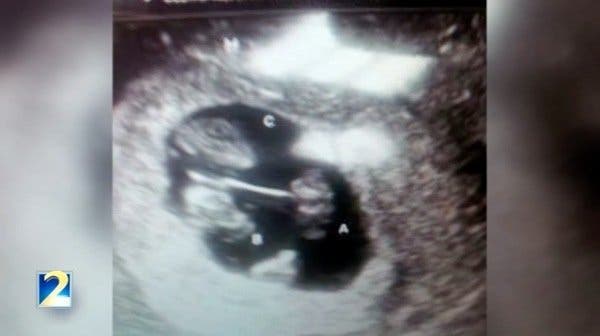

Le docteur découvre que Joanie est enceinte de triplés. C’est un cas rare, surtout associé à la condition physique de Joanie qui l’empêchait de tomber enceinte. Il y a tout juste une chance sur 200 millions d’avoir des triplés !

Mais plus il y a d’enfants dans l’utérus de la mère, plus le risque de complications pendant la grossesse est élevé. La famille très heureuse de l’annonce s’inquiète, malgré tout, énormément pour la santé de Joanie et des trois enfants.